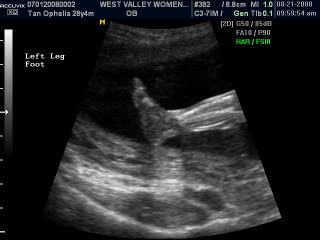

His left leg! So cute...